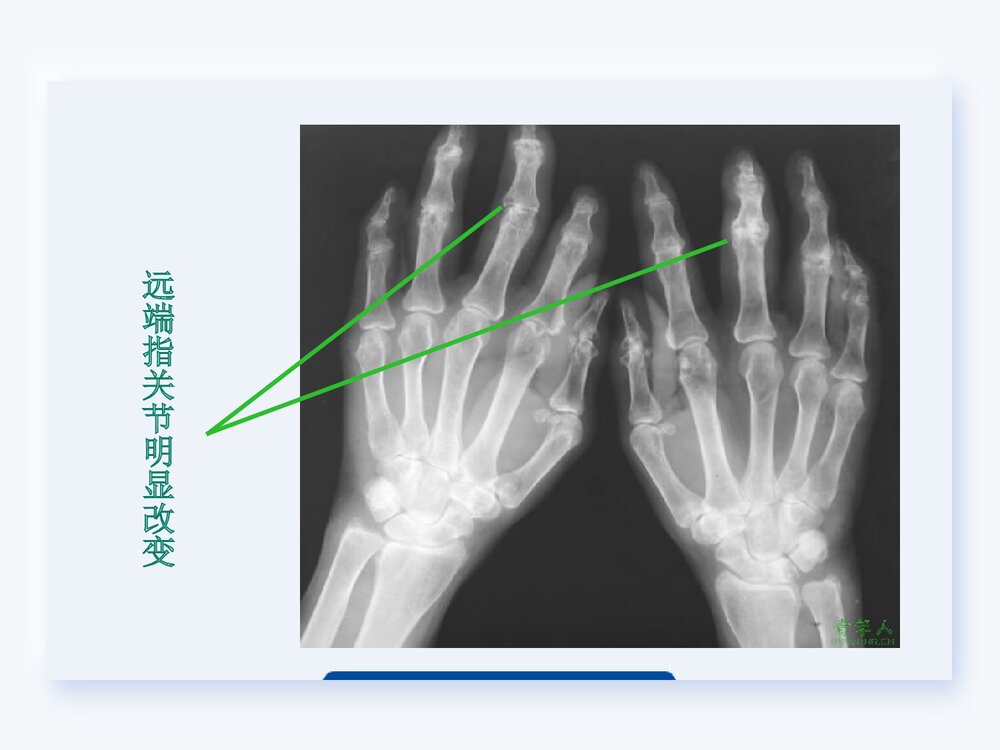

类风湿关节炎的护理查房类风湿关节炎的护理查房定义类风湿性关节炎(rheumatoidarthritisRA)是一种以关节滑膜炎为特征的慢性全身性自身免疫性疾病。临床上常以对称性、周围性、慢性、多关节炎性病变为主要特征,可表现为受累关节疼痛、肿胀以及功能下降。尚无定论,可能与感染因子、遗传因素、激素有关。病因发病机制发病机制尚不十分清楚,但多数人认为RA是一种自身免疫性疾病。临床表现大多数患者表现为对称性多关节炎。主要侵犯小关节,以腕关节、近端指间关节、掌指关节最常见。其次为膝、踝、肘、肩、髋、及颞颌关节。一、关节表现血管翳显微镜下病理性改变(1)晨僵:95%以上的患者可出现晨僵。持续时间多数大于一小时,活动后可减轻。晨僵持续时间与关节滑膜炎症严重程度成正比,是观察本病活动的一个重要...